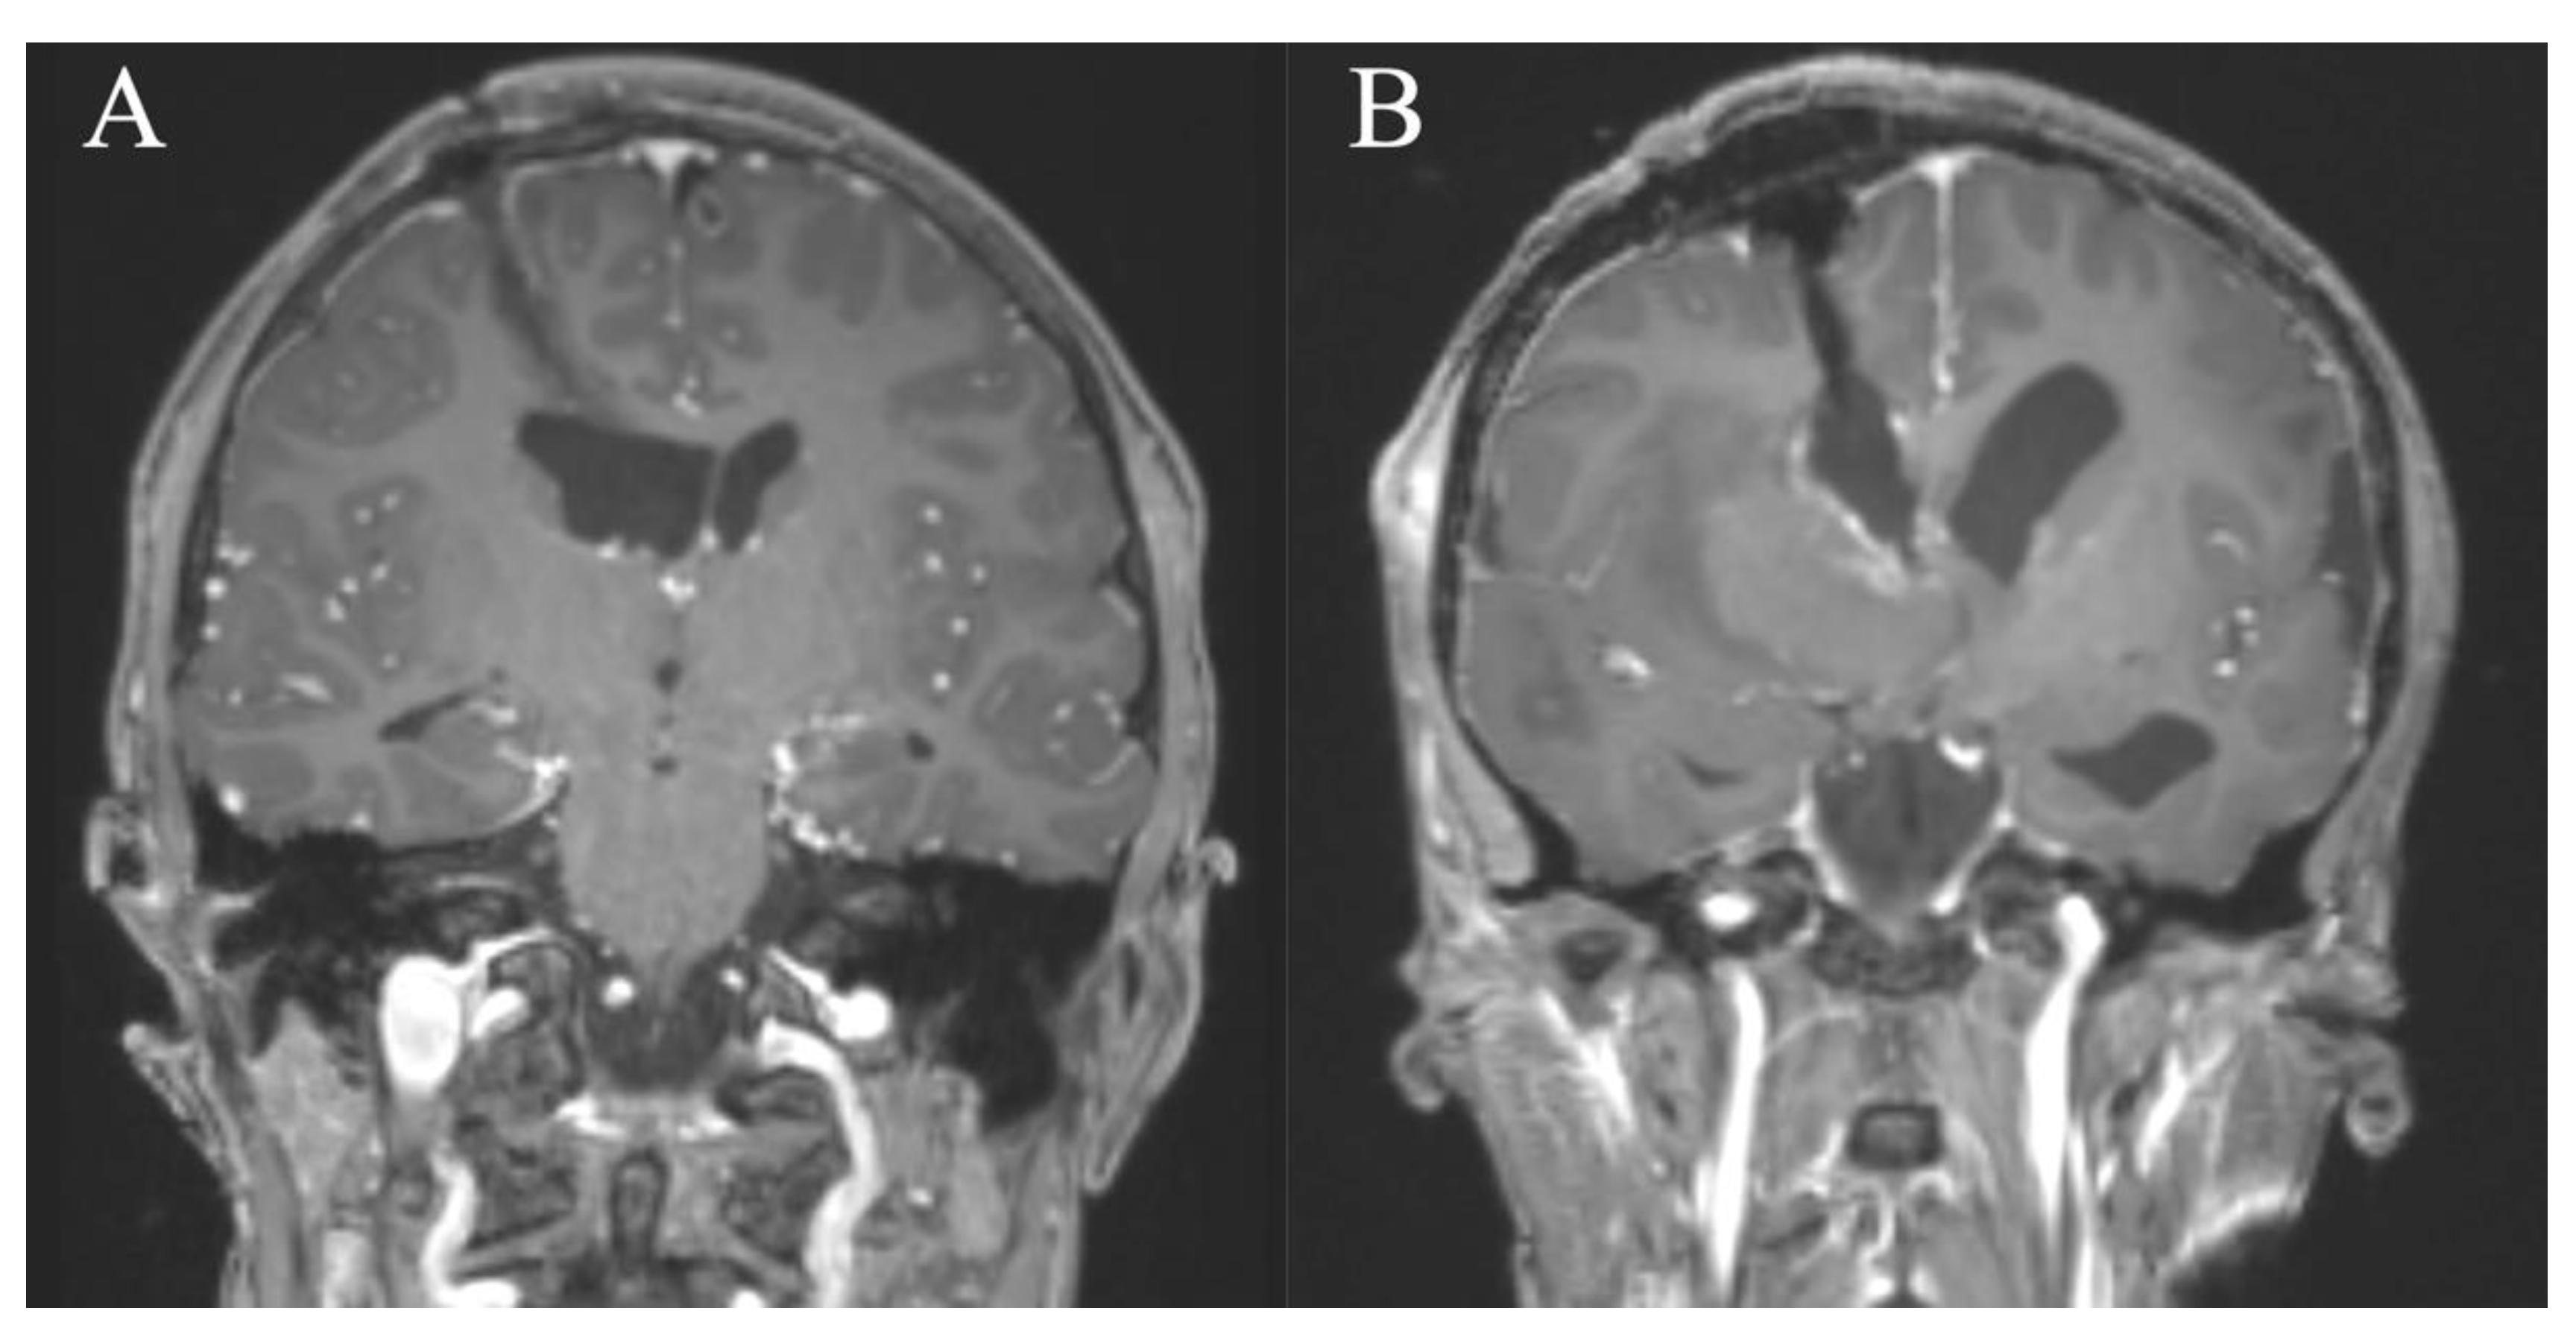

In contrast to the EA technique, the PE technique involves only a very small skin incision, a burr hole, and small corticotomy which results in minimal tissue damage (Figure 7). We hypothesize that the minimally invasive approach of the PE technique and the associated minimal tissue damage will reduce the risk of wound healing problems, CSF fistulas, parenchymal bleeding, and further surgery-related complications compared to the EA technique.

In comparison, the range of motion of the endoscope through a PE approach is limited. Using an EA approach with a mini-craniotomy, the range of motion and the viewing angles with the endoscope is wider, and there is better control in the event of bleeding. In addition, an EA technique can be used to remove large parts of a lesion using the microscope, if needed. The resection of the lesion can then be done using both the microscope and the endoscope, which might be essential for lesions with characteristics as descried in Table 1.

Figure 7. Cases 8 and 7. Coronal MR images, T1-weighted sequences with contrast medium immediately postoperatively (A,B) after resection of an intraventricular lesion through a frontal right approach in a pure endoscopic (A) and endoscopic-assisted fashion (B). A PE approach tends to result in less tissue damage to the cortex and parenchyma due to the small diameter peel-away sheath (A) compared to the endoscopic-assisted approach using the Vycor speculum (B).